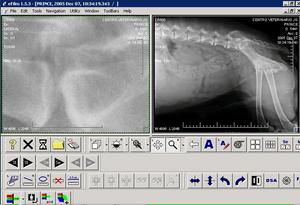

IMAGEN DICOM OBTENIDA. Se puede aumentar la calidad de la imagen variando el contraste o la iluminación |

MANEJO INFORMÁTICO DE LA IMAGEN. La imagen DICOM se exporta a un servidor DICOM que tiene software específico para este formato. |

DICOM. La imagen DICOM se puede examinar de múltiples formas: ampliando, en copia negativa, realzando , etc.. Sólo se puede manejar con software DICOM. |